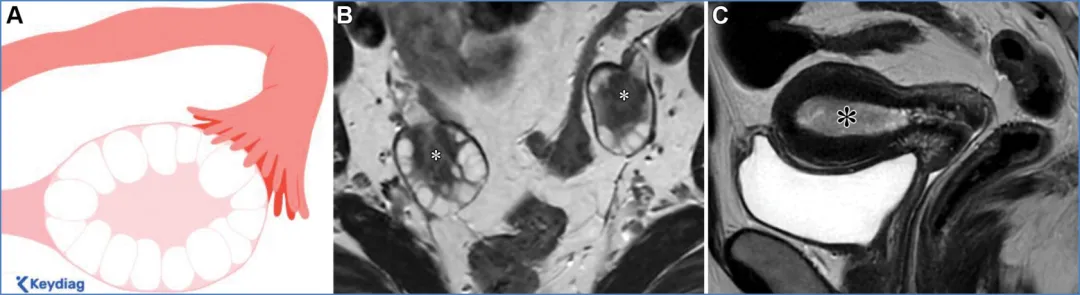

卵巢——卵巢是可活动的腹膜内器官,由卵巢韧带(连接卵巢与子宫角)、卵巢系膜(将卵巢固定于阔韧带)和悬韧带(连接卵巢与盆腔侧壁并包裹性腺血管)支撑(图6)(36)。性腺动脉起源于肾动脉下方的腹主动脉;右侧性腺静脉汇入下腔静脉,左侧性腺静脉汇入左肾静脉。性腺静脉直径大于0.8厘米为异常,尽管性腺静脉直径与静脉反流之间的相关性较差(37)。性腺血管走行于腰大肌前方、输尿管外侧。 卵巢的表现随月经周期阶段和绝经状态而变化。绝经前卵巢为较大的椭圆形结构,在T2加权成像上能清晰显示分区解剖结构,包括T2低信号的皮质、T2等信号的髓质(含疏松排列的基质和血管)、T2高信号的薄壁卵泡,偶尔可见黄体(19,38)。黄体因有黄素化的卵泡膜细胞而呈现T2等信号的厚壁,在退化过程中会变得锯齿状。非出血性黄体中央呈T1低信号、T2高信号,而出血性黄体中央呈T1和T2高信号,有时可见血细胞比容平面。静脉注射对比剂后,卵巢皮质和基质轻度强化,强化程度低于子宫肌层,而黄体壁则表现为早期明显强化(38)。绝经后卵巢比绝经前卵巢小,皮质和髓质呈T2等信号至低信号,偶尔可见小囊肿(38)。表S2以及图7-10详细描述了常见的生理性和其他良性卵巢表现的MRI特征(19,38-42)。图7. 两位不同患者的正常经前卵巢,突出显示了生理学观察结果。(A)示意图显示了带有卵泡的经前卵巢。(B)一位27岁女性患者的轴位T2加权图像显示一个椭圆形卵巢,具有T2低信号皮质(箭头)、T2等信号髓质(白色*)和多个T2高信号卵泡(黑色*)。(C、D)一位30岁女性患者的轴位T2加权(C)和对比增强脂肪抑制T1加权(D)图像显示了黄体(CL),这是经前女性常见的生理学表现。其影像学表现随发育阶段而变化。典型的黄体在T2加权成像上表现为囊性结构,中心呈高信号,壁厚且呈锯齿状,信号强度中等(C中的箭头),在静脉注射造影剂后明显强化(D中的箭头)。图8. 一名34岁闭经女性患者的多囊卵巢综合征与继发性非典型子宫内膜增生。(A)示意图展示了多囊卵巢,这是一种常见的内分泌疾病,影响高达10%的育龄女性。多囊卵巢综合征的诊断依据Rotterdam标准,该标准要求满足以下三项中的至少两项:多囊卵巢、月经稀发或无排卵,以及高雄激素血症。多囊卵巢的定义为:至少一侧卵巢的体积达到10毫升或以上,或者每个卵巢有20个或更多的卵泡(详见表S2)。(B)轴位T2加权图像显示双侧多囊卵巢增大,中央为T2等信号基质(小*),周围有多个T2高信号卵泡。(C)矢状位T2加权图像显示子宫内膜腔内呈不均匀的T2等信号(大*),对应活检证实的非典型子宫内膜增生。在所有增强后序列(包括延迟图像,未显示)中,非典型子宫内膜增生的强化程度低于子宫肌层,这与子宫内膜癌的强化模式相似。图9. 一名27岁女性患者的右侧卵巢扭转,该患者表现为急性盆腔疼痛。轴位T2加权图像显示右侧卵巢(RO)增大且水肿,伴有外周卵泡(箭头所示)。与正常的左侧卵巢(*)相比,右侧卵巢位置异常,位于子宫(U)的中央后方。卵巢扭转的其他表现(未显示)可能包括血管蒂扭转以及强化程度不一,这取决于缺血程度或是否存在梗死。图10. 一位43岁女性患者的输卵管卵巢脓肿,该患者在子宫内膜活检后出现恶心、呕吐和盆腔疼痛症状。轴位T2加权像(A)和对比增强脂肪抑制T1加权像(B)显示左侧附件区有一个多房囊性肿块。该肿块内含有脓性液体,在T2加权像上表现为不同的信号强度(A中的*),并具有增厚的强化壁以及多个强化分隔(B中的箭头)。高b值扩散加权像和ADC图(未显示)显示扩散受限,与脓液的存在相符。经皮引流后获得的细菌培养结果显示大肠杆菌阳性。——输卵管从子宫角延伸至卵巢(39)。近端的壁内部分穿过子宫肌层;远端带有伞端的漏斗部开口于卵巢附近的腹膜腔。输卵管被阔韧带的输卵管系膜包绕(图6)。在MRI上,它们表现为卵巢和子宫之间的T2低信号管状结构。子宫体和宫颈解剖。——子宫由子宫体和宫颈组成,宫颈下段(或子宫颈外口部)突入阴道上部(图2、3)(24、25、43)。在T2加权成像上,绝经前子宫的子宫体(子宫内膜、结合带和外肌层)和宫颈(宫颈管、宫颈内间质和宫颈外间质)均显示出清晰的分区解剖结构。绝经后或接受放射治疗后,这种分区解剖结构会变得不清晰(24、25、43)。子宫内膜腔由均匀的T2高信号子宫内膜衬里,延伸至同样为T2高信号的宫颈管(38)。子宫内膜厚度在子宫矢状面中部沿子宫长轴测量,其数值会随绝经状态和月经周期阶段而变化(表S3)(38、44-49)。对于有绝经后出血的患者,子宫内膜厚度≥5mm为异常;而无症状患者的阈值则不太明确(50)。结合带(子宫内肌层)呈T2低信号,向尾侧延续为T2低信号的宫颈内纤维间质。子宫外肌层呈T2等信号,过渡为宫颈外间质的T2等信号。正常结合带厚度≤8mm,若无微囊肿则可达11mm(45)。 子宫峡部是子宫体与宫颈之间的过渡区,在矢状位T2加权成像上表现为局限性缩窄,在轴位斜向T2加权成像上可见子宫血管进入(图2、3)(24、25)。宫颈内口和外口分别是宫颈管的上下开口。宫颈围绕宫颈管,包括上皮衬里和宫颈间质(43)。宫颈上段由腺状柱状上皮覆盖,宫颈下段(包括子宫颈外口部)由鳞状上皮覆盖。鳞状上皮与柱状上皮的交界处(鳞柱交界)在生育年龄具有动态变化,是大多数宫颈癌前病变和宫颈癌的起源部位。宫旁组织由主韧带和宫骶韧带构成,从宫颈两侧延伸至盆侧壁,包绕子宫血管、神经和输尿管(图2、3)。表S3以及图11-13概述了常见的子宫体和宫颈良性病变的MRI特征(38、44-49)。图11. 一位50岁女性患者的子宫内膜息肉,该患者在乳腺癌切除术后接受他莫昔芬治疗。(A)子宫矢状面示意图显示息肉状子宫内膜病变,伴有因子宫内膜腺体扩张而形成的囊性病灶。(B)冠状斜位T2加权像显示子宫内膜内有一个带蒂病变,具有T2低信号的纤维血管核心(白色箭头)和T2高信号病灶(黑色箭头),这些表现提示为子宫内膜息肉。通常可见明显的强化,与子宫肌层的强化程度相似(未显示)。明确诊断需要宫腔镜下切除,因为子宫内膜息肉、增生和肿瘤可能同时存在,且在影像学特征上可能重叠。偶然可见子宫腺肌症,表现为结合带内存在微囊肿(箭头所示)。图12. 弥漫性和局灶性子宫腺肌病(或子宫腺肌瘤)。(A)子宫矢状面中部的插图显示了弥漫性子宫腺肌病(上图)与局灶性子宫腺肌病或子宫腺肌瘤(下图)的对比。(B、C)两名不同的月经过多患者的矢状位T2加权图像显示,T2低信号的交界区(JZ)弥漫性增厚,伴有散在的T2高信号微囊肿(B中的实线),以及前部交界区伴有微囊肿的局灶性肿块样不对称增厚(C中的虚线)。这些表现是由于子宫肌层内存在异位子宫内膜腺体和间质(微囊肿)以及反应性平滑肌增生(交界区增厚)所致。图13. 纳博特囊肿与隧道簇。插图(A)及两名不同患者的子宫正中矢状面T2加权图像(B、C)显示,浅层宫颈基质内的单房囊肿为典型的纳博特囊肿(A图左图;B图),而向宫颈基质深部延伸的多房囊肿为隧道簇的特征性表现(A图右图;C图)。务必在增强图像上排除强化实性组织的存在(未显示),因为多房性宫颈病变中若出现强化实性组织,应怀疑宫颈胃型腺癌。可能需要进行宫颈锥形活检以明确诊断。子宫在骨盆内的位置会因膀胱充盈程度和盆腔瘢痕情况而有所不同。倾位指的是宫颈与阴道之间的角度:前倾位是向前倾斜,后倾位是向后倾斜(图14)(38)。屈曲描述的是子宫体与宫颈之间的角度:前屈是向前弯曲,后屈是向后弯曲(38)。图14. 插图(A)和磁共振图像(B、C)显示了女性骨盆内子宫的各种位置。子宫倾(Version)指的是宫颈与阴道之间的角度:A中的上组插图将该角度显示为黄线相对于红线的倾斜度。前倾(Anteversion)指向前倾斜,后倾(Retroversion)指向后倾斜。子宫屈(Flexion)描述的是子宫体与宫颈之间的角度:A中的下组插图将该角度显示为蓝线相对于黄线的倾斜度。前屈(Anteflexion)指向前弯曲,后屈(Retroflexion)指向后弯曲。两名患者的矢状位T2加权图像(B、C)中,B显示的是前倾前屈位子宫,C显示的是后倾后屈位子宫。阴道是一个纤维肌性结构,通过膀胱阴道隔与膀胱相隔,通过直肠阴道隔与直肠相隔(图4)(51)。在轴位T2加权成像上,绝经前阴道通常呈H形或W形塌陷,具有高信号的黏膜皱襞和低信号的壁。绝经后,皱襞消失,阴道壁厚度变薄。阴道上部有由突出的宫颈形成的穹窿,阴道下部通过阴道口开口于外阴前庭。表S4和图15详细描述了常见良性阴道病变的MRI特征(51-53)。图15. 四个不同患者的矢状面示意图(A)和轴位T2加权图像(B–E)显示了阴道囊肿、斯基恩氏腺囊肿以及尿道憩室。巴氏腺囊肿:位于耻骨联合处或其下方阴道后外侧壁的单房囊肿(A中的灰色椭圆形,B中的T2高信号囊性病变)。加特纳管囊肿:位于耻骨联合处或其上方阴道前外侧壁的单房囊肿(A中的蓝色椭圆形,C中的T2高信号囊性病变)。斯基恩氏腺囊肿:位于耻骨联合下方、阴道前方、尿道下段外侧的单侧或双侧小单房囊肿(A中的浅黄色椭圆形,D中的T2高信号囊性病变)。尿道憩室:在耻骨联合附近,尿道中远端后外侧出现的圆形、椭圆形或U形T2高信号液性囊袋状突起(A中的尿道囊袋状突起)。在罕见情况下,尿道憩室可能完全环绕尿道(E中的T2高信号环形囊性病变)。外阴由女性外生殖器组成(图16)(53)。阴阜位于耻骨联合前方,由脂肪组织构成。大阴唇是位于阴阜下方并与其相连的厚皮肤皱襞。小阴唇是大阴唇之间较薄的皱襞,向前会合于阴蒂头。小阴唇之间的前庭包含尿道外口(尿道口)和阴道口(阴道开口)。图16. 示意图(A)和轴位T2加权图像(B)显示了外阴区域或女性外生殖器。阴阜位于耻骨联合前方,由脂肪组织构成。大阴唇是位于阴阜下方且与其相连的厚皮肤皱襞。小阴唇是大阴唇之间较薄的皱襞,向前汇聚于阴蒂头。小阴唇之间的前庭前部有尿道外口(尿道口),后部有阴道口(阴道开口)。参考文献:https://doi.org/10.1148/rg.250029